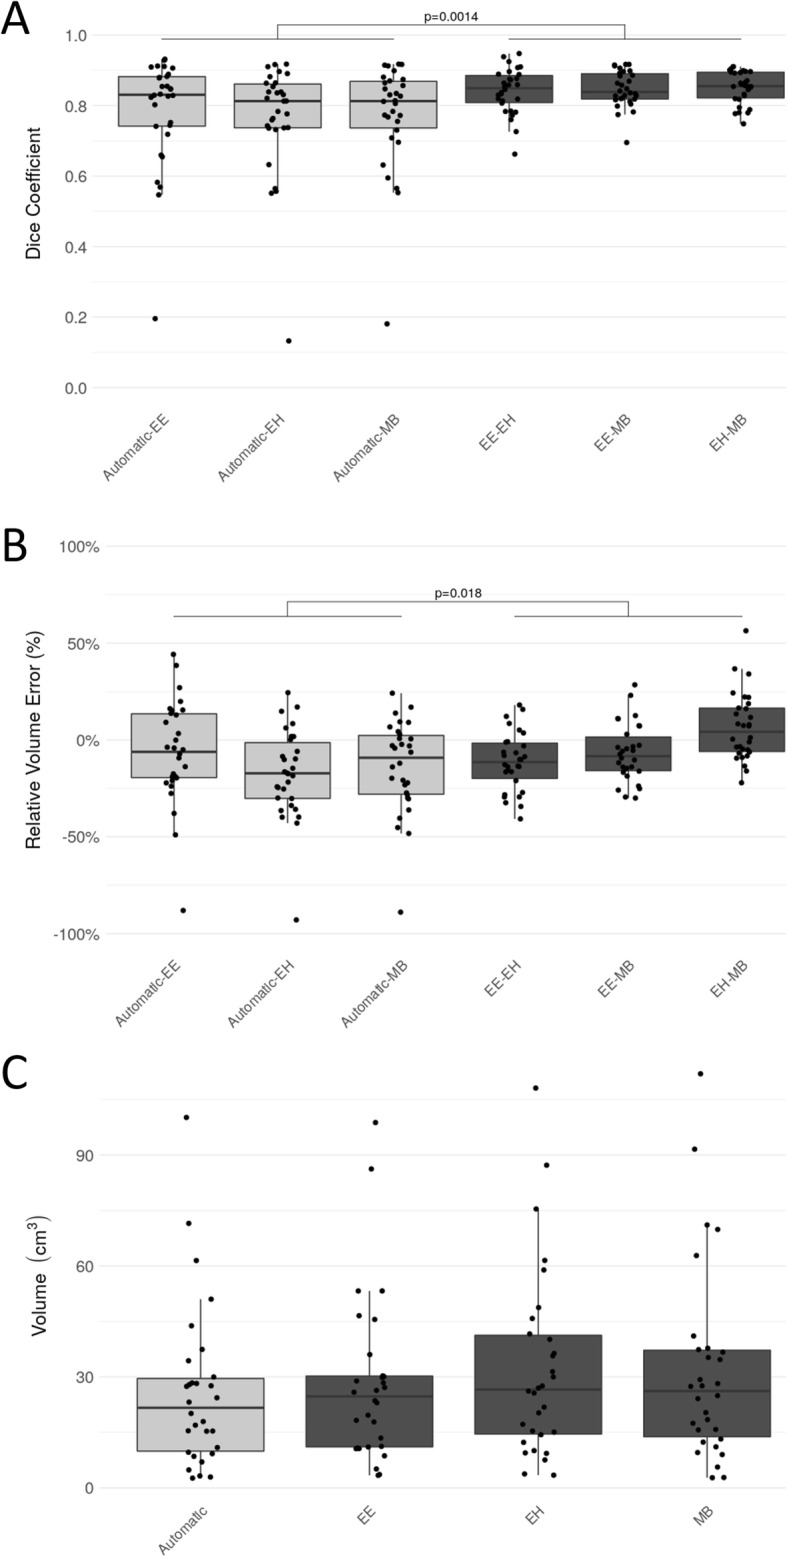

The DC and the relative volume error of the different pairings of expert raters and the automatic segmentation are listed in Table 2. The median overall DC among the raters was 0.85 (interquartile range [IQR]:0.07). The median DC between the automatic segmented RCs and the fused reference segmentation was 0.84 (IQR: 0.10), and slightly lower than the agreement among raters. In terms of relative volume error, we found a median error of − 13.17%, (IQR: 24.17%) between automatic and reference segmentations, which indicates the DL method underestimated the RC with respect to the raters. The median of the absolute volume was 24.7cm3 (IQR: 19.1cm3) for EE, 26.6cm3 (IQR: 26.7cm3) for EH, 26.1cm3 (IQR: 23.3cm3) for MB and 21.7cm3 (IQR: 19.6cm3) for the automatic segmentation. Figure 2 shows boxplots of DC values, relative volume errors and the absolute volumes for the automatic approach in relation to the experts. According to the Kruskal Wallis test we did not detect a statistically significant difference regarding the distribution of the measured volumes for the different raters and the automatic method (chi-square = 1.46, p = 0.69). In contrast, a statistically significant difference in DC (chi-square = 11.63, p = 0.04) and relative volume error (chi-square = 22.45, p = 0.00043) was found. The result of the subsequent Wilcoxon rank-sum test between rater-to-rater (EE-EH, EE-MB, EH-MB) and automatic-to-rater (Automatic-EE, Automatic-EH, Automatic-MB) pools are shown in Figs. 2 and 3. The automatic segmentation volumes tend to be smaller than the expert volumes, which corresponds with the underestimation found in the relative volume error measurement. The main sources of error by the automatic method were localized to signal inhomogeneity (especially in T2w and FLAIR sequences) and other intensity patterns (edema, subarachnoid space, or ventricles). Figure 4 shows cases representing good and bad performances.

Fig. 2.

Comparison of the automatic approach and the three experts (EE, EH, MB) in terms of Dice coefficient (a), relative volume error (b), and absolute volume (c) on the cross-evaluated cohort. The light gray boxes on the left represent results of automatic method and the dark gray boxes on the right show the experts. P-values indicate the result of the Wilcoxon rank-sum test (α = 0.05) between automatic-rater (Automatic-EE, Automatic-EH, Automatic-MB) and rater-rater (EE-EH, EE-MB, EH-MB) results

Median and interquartile range of the Dice coefficient (DC) and relative volume errors (Rel. vol. err.) for the three experts (EE, EH, MB) and the automatic approach.